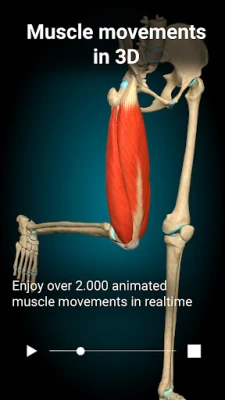

A true and totally 3D app for studying human anatomy, built on an advanced interactive 3D touch interface.

★ You can rotate models to any angles and zoom in and out

★ Muscles

★ Muscles